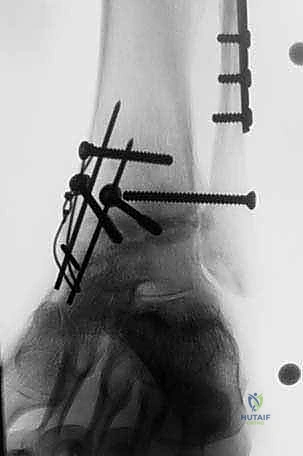

- في بعض الحالات المعقدة، قد يتطلب الأمر إجراء قص عظمي في الكعب (Malleolar Osteotomy) لفتح المفصل بالكامل ورؤية السطح المتضرر بوضوح، ثم يتم إعادة تثبيت هذا العظم لاحقاً.

4. زراعة الطعم وتثبيته (Graft Implantation and Fixation)

- يتم تشكيل الطعم المأخوذ من المتبرع ليطابق الحفرة التي تم إعدادها في كاحل المريض تماماً (مثل تركيب قطعة البازل).

- يتم إدخال الطعم برفق (Press-fit).

- لضمان الثبات التام، يتم تثبيت الطعم باستخدام براغي دقيقة جداً (غالباً تكون قابلة للامتصاص البيولوجي أو براغي تيتانيوم غاطسة تحت مستوى الغضروف حتى لا تحتك بالمفصل).

صور إضافية من داخل غرفة العمليات والخطوات الجراحية

ندرك أهمية توثيق الخطوات الجراحية لطلاب الطب والمرضى الراغبين في فهم دقة الإجراء. هذه الصور توضح مراحل زراعة وتثبيت الطعم العظمي الغضروفي بدقة متناهية تحت إشراف أ.د. محمد هطيف.